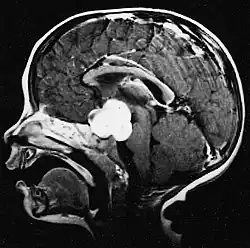

Auf -Kernspintomogrammen erscheint ein intrakranieller Tumor als massive Läsion, die nach Verwendung des Kontrastmittels lumineszierender werden kann. Eine Signalanomalie gibt es jedoch immer in -Kernspintomogrammen, die auf das Vorhandensein einer Neoplasie oder eines vasogenen Ödems hinweist. Normalerweise ist eine stärkere Lumineszenz (Kontrastverstärkung) ein Hinweis auf einen Tumor höheren Malignitätsgrades. Ein Kontrastring ist charakteristisch für ein Glioblastom, wobei der Lumineszenzanteil dem lebenswichtigen Teil des bösartigen Tumors und der dunklere -hypointense Bereich der Gewebenekrose entspricht.[4]

Glioblastome

Die sowohl häufigsten als auch bösartigsten Gliazelltumoren sind Glioblastome. Sie bestehen aus einer heterogenen Masse schlecht differenzierter Astrozytomzellen hauptsächlich bei Erwachsenen. Normalerweise treten sie in den Gehirnhälften auf, seltener am Hirnstamm oder Rückenmark. Außer in sehr seltenen Fällen dehnen sie sich wie alle Hirntumoren nicht über die Strukturen des Zentralnervensystems hinaus aus.[22]

Das Glioblastom kann sich aus einem diffusen (II. Grades) oder einem anaplastischen Astrozytom (III. Grades) entwickeln. In letzterem Fall wird es als sekundär bezeichnet. Tritt es jedoch ohne Vorstadien oder ohne Anzeichen einer früheren Malignität auf, bezeichnet man es als primär. Glioblastome werden mittels Operationen, Bestrahlung und Chemotherapie behandelt. Sie sind schwer zu heilen und es gibt nur wenige Überlebensfälle von über drei Jahren.[23]